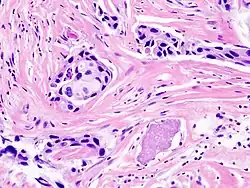

Los sistemas de digitalización para microscopía virtual actuales permiten el "escaneo" automático de muestras preparadas y provenientes de citología o histología creando una preparación virtual en cuestión de minutos. Con ello, es posible digitalizar todo tipo de preparaciones histológicas o citológicas, desde gruesos cortes (15 μm) de tejidos incluidos en parafina, hasta finos cortes de 5 μm de histología o histopatología convencional con tinciones como hematoxilina eosina, inmunohistoquímica o de inmunofluorescencia.

Una preparación virtual es uno o un conjunto de archivos que contienen toda la información en imágenes de toda una preparación. Un sistema informático conectado a un microscopio realiza el barrido mediante fotografías de toda la preparación, y las organiza de manera que, mediante un software especial, es posible obtener tener una imagen a bajo aumento a modo de mapa de la preparación y los sucesivos altos aumentos. Una de las ventajas más inmediatas de este sistema es que permite obtener fotografías a bajo aumento con un enfoque perfecto, pues el bajo aumento proviene del ensamblado de imágenes bien enfocadas a alto aumento. Los archivos obtenidos tienen un peso (tamaño) muy elevado que puede oscilar entre 200 MB y 40 GB.